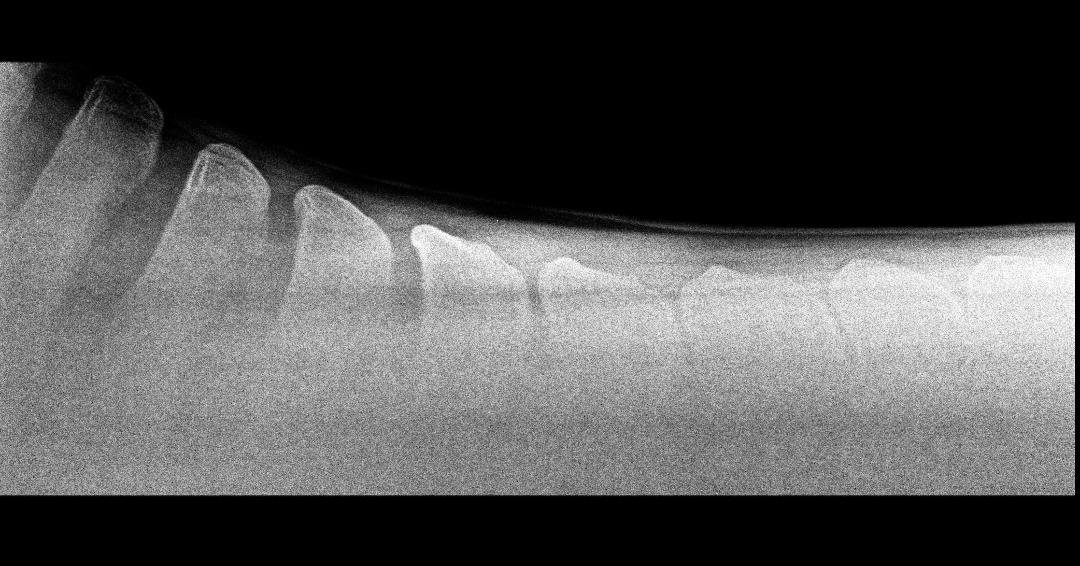

Let’s start with the basic anatomy of the horse’s spine and then focus on what is actually happening in the horses body with the presence of this condition. The dorsal spinous processes are the sections of bone that we can feel along the line of the spine, and are vertical projections of bone emanating up from the spinal vertebrae deep in the horses back.

ORDSP stands for Over-Riding Dorsal Spinous Processes and this is a term used to describe ‘kissing spine’. What it means is the touching of the bones along the spine, which causes back pain to the horse. This condition quite often happens when the horses back is weak and the whole middle section of the horse, the trunk, is in a sunken position – this brings the bones in the spine closer together, causing pain if the bones touch.

Usually a postural change has occurred that brings the dorsal spinous processes closer together, ultimately allowing the bones to touch, which is extremely painful for the horse, and over time the bones can actually remodel and fuse.

The only way to properly diagnose this condition is to have your horse’s spine x-rayed. This will provide a clear image to the veterinary surgeon of where your horses dorsal spinous processes sit in relation to one another. The common area for KS is in the thoracic spine, under the saddle area.